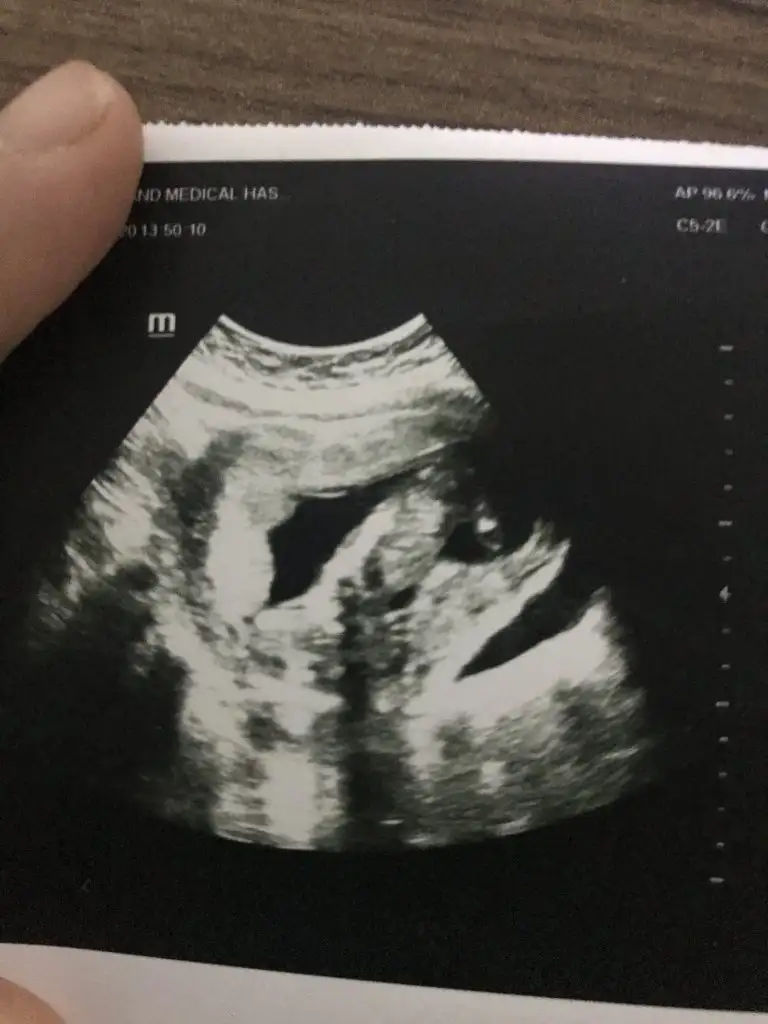

dün gittik 14 hafta usg verdi ama belli olmuyor

Kız bence 9+6 hafta ya göre

Buda kız gibi boş görünüyor bacak arasıdün gittik 14 hafta usg verdi ama belli olmuyor Eki Görüntüle 2575104